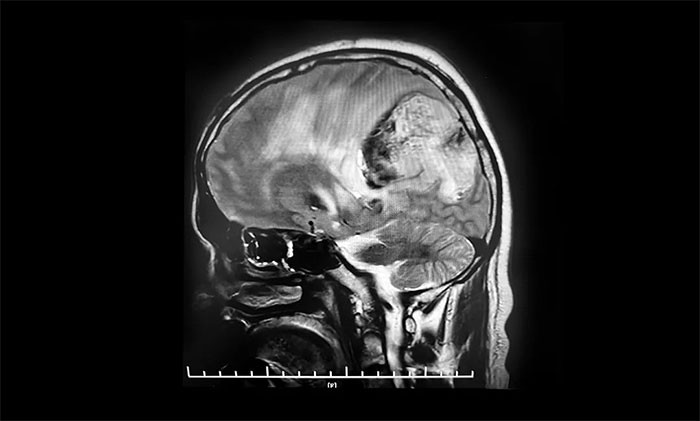

頭顱MRI平掃+增強+DWI+MRA提示,左側頂枕葉巨大腫瘤伴局部瘤卒中,幕上腦室系統(tǒng)、腦干受壓變形,中線結構右移19mm,大腦鐮下疝形成。李士其教授等專家團隊會診指出,患者腦內(nèi)巨大占位,性質(zhì)不明,并且患者已經(jīng)發(fā)生腦疝昏迷,生命危在旦夕,應盡快進行手術治療,挽救患者生命,同時明確病理診斷。

▲ 左側頂枕葉巨大腫瘤伴局部瘤卒中